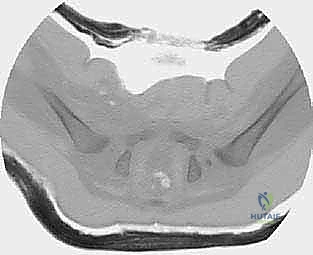

1. الفحص بالموجات فوق الصوتية (Ultrasound)

بالنسبة للرضع الذين تقل أعمارهم عن 4 إلى 6 أشهر، يُعد التصوير بالموجات فوق الصوتية هو المعيار الذهبي. لماذا؟ لأن عظام الحوض ورأس الفخذ تكون في هذه المرحلة غضروفية ولا تظهر بشكل واضح في الأشعة السينية.

تسمح الموجات فوق الصوتية للدكتور هطيف برؤية الغضاريف بوضوح، وتقييم عمق التجويف الحقي (باستخدام زوايا جراف - Graf angles)، ورؤية استقرار المفصل أثناء حركة الساق (الفحص الديناميكي). يتميز هذا الفحص بأنه آمن تماماً ولا يعرض الطفل لأي إشعاع.